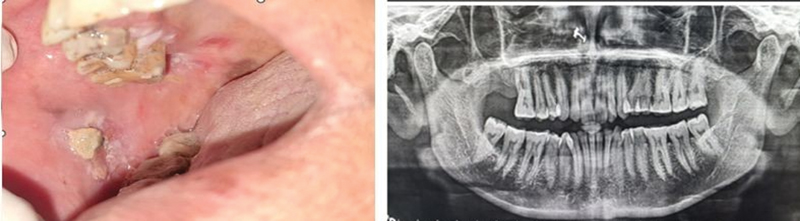

| Figure 3: Clinical and radiographic images of a 48-year-old female patient with cancer of the lower right alveolus and the floor of the mouth with no known risk factors other than periodontitis.